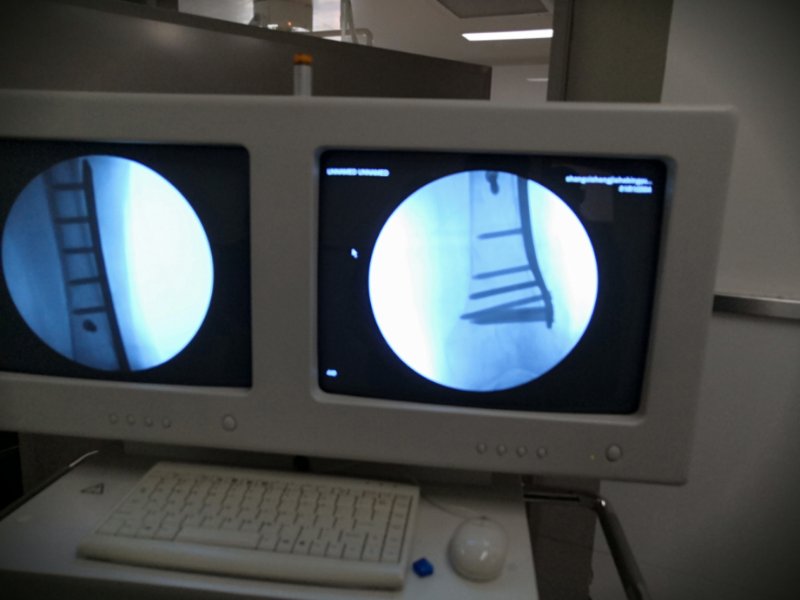

科室刘军政主任了解到这些情况后高度重视,积极进行术前准备,完善相关检查,针对患者病情,身体条件及一般情况充分多次评估后,亲自主刀,为患者施行股骨下段切开复位钢板内固定术,术中仔细解剖,严密止血,充分清理骨折断端坏死组织,选用合适长度锁定钢板固定,C型臂透视证实对位,对线良好,手术历时1小时20分钟顺利结束。术后为其制定了严密的治疗护理计划,包括营养支持,预防感染,肢体锻炼等一系列措施,帮助其快速恢复。